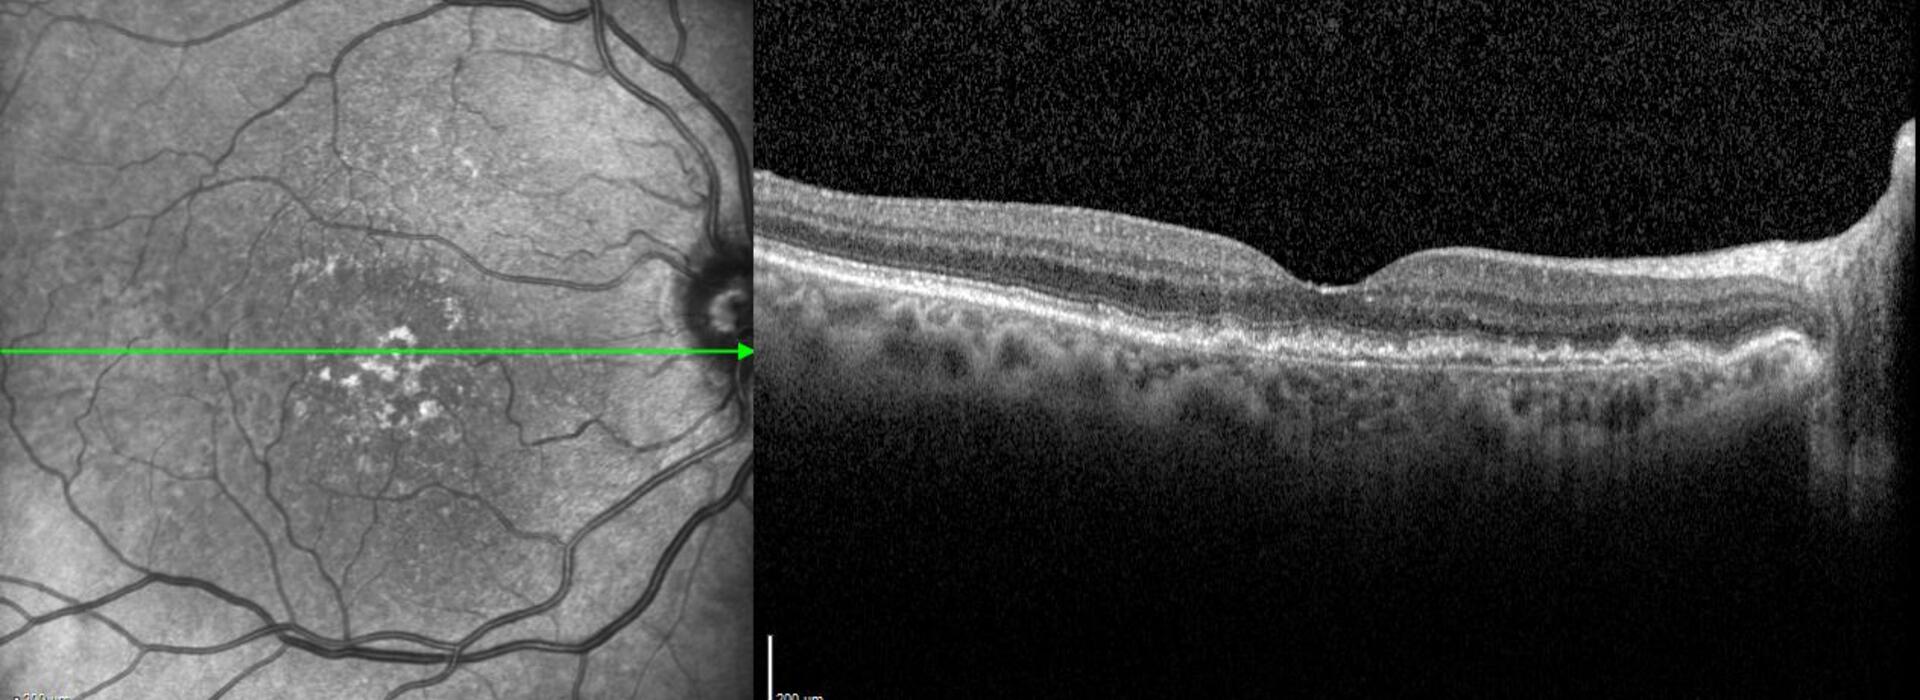

La Dra Rosa Dolz revisa el estado actual de la clasificación de la DMAE en base no solamente a los signos en la retinografía sino incorporando los signos estructurales tomográficos fundamentales

Clasificación actualizada de la DMAE